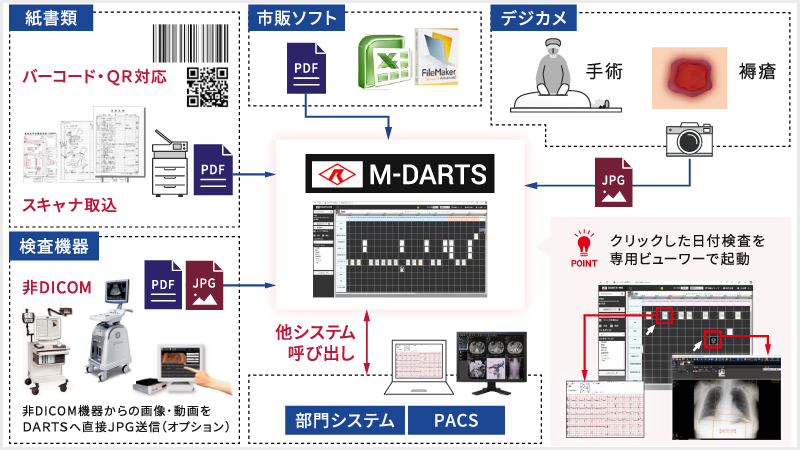

■統合Viewer M-DARTS

DICOMキー画像をはじめ、スキャン画像データやデジカメ画像データ等の非DICOM画像を一元管理・表示する統合Viewerです。

患者様単位で、登録情報をマトリックス上で直感的に表示します。